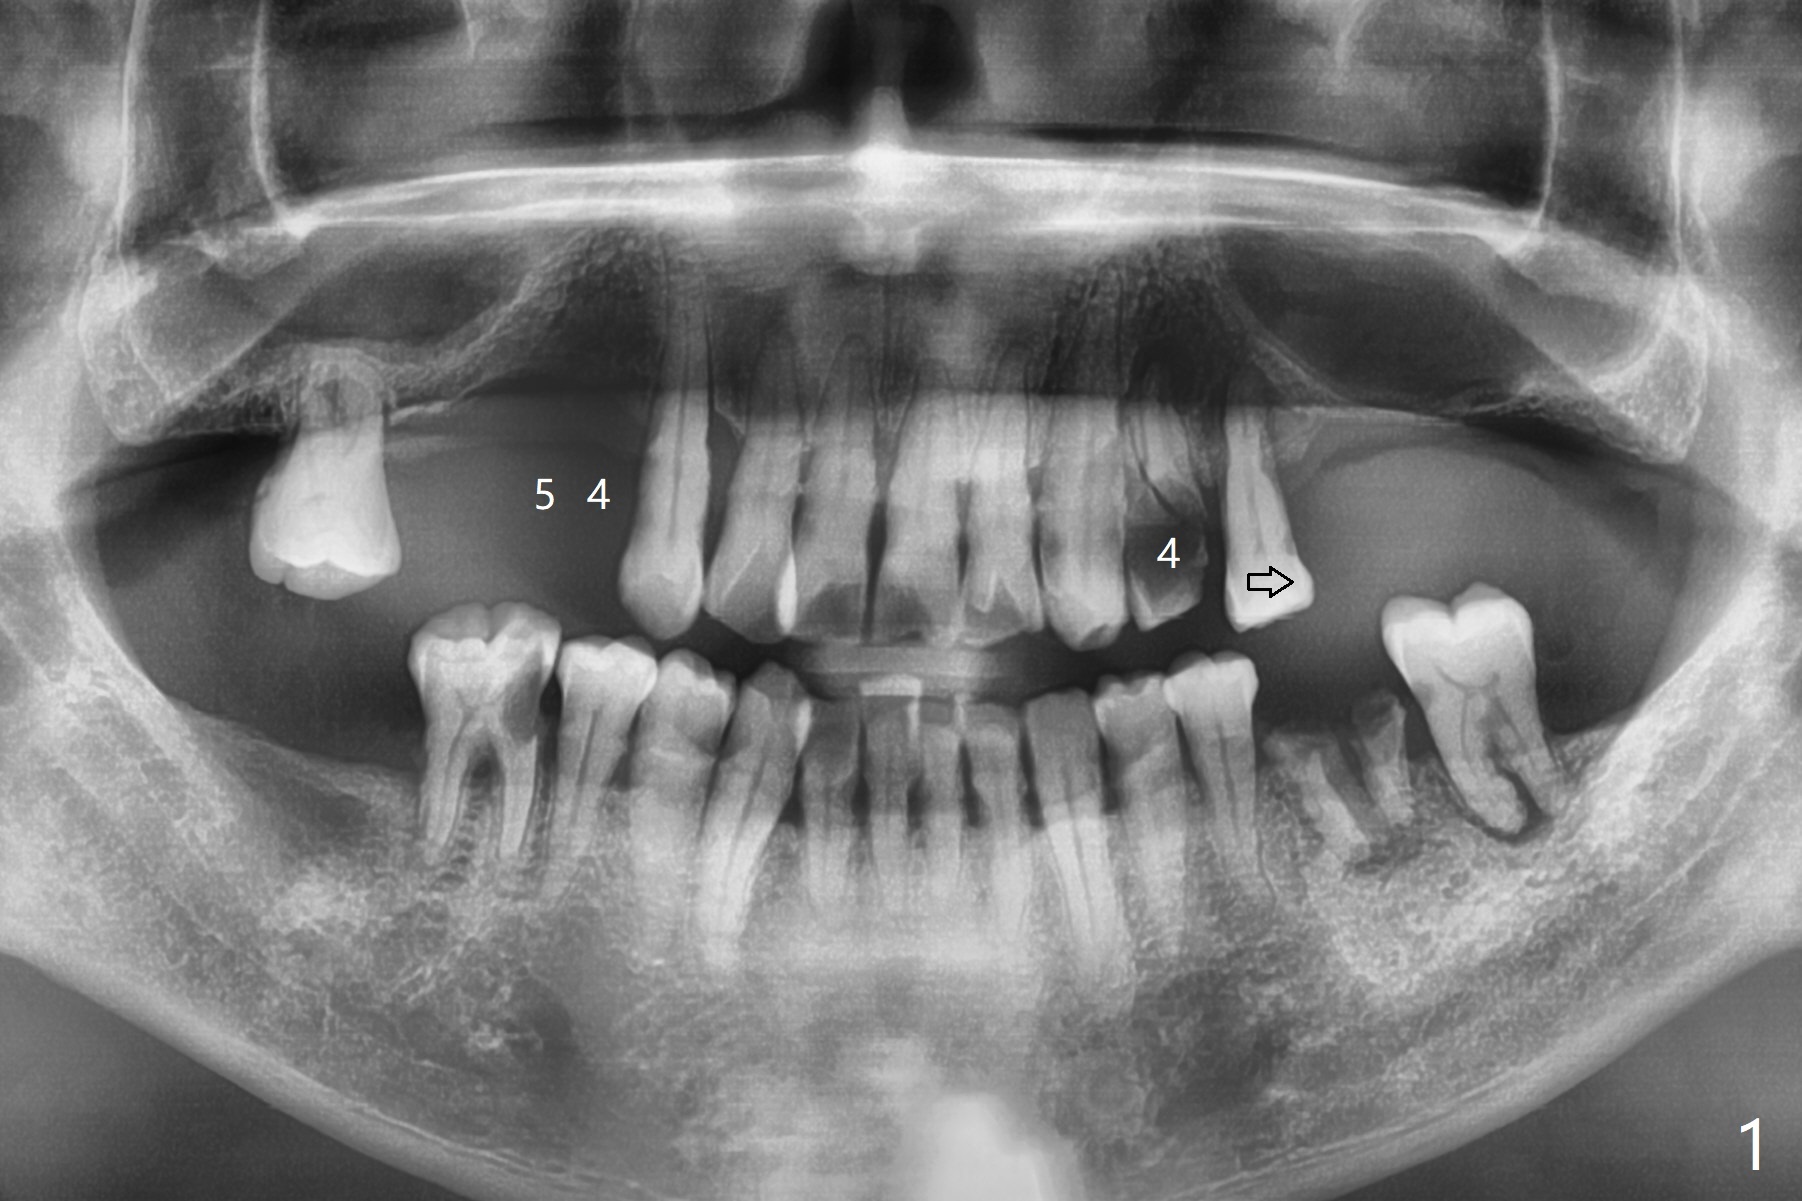

58岁男,吸烟,要求拔除断裂左上4(图一,二),邻牙(5)骨质吸收严重(图一,四),右上4,5拔除后骨质吸收(图一),所以左上4拔除(图三)位点保留(图四:人工骨,图五:GEM Cap)重要,尽管他准备做假牙。

今天手术缺点局麻不足,出血控制不好。明天一早同样病例,左上4拔除,使用两只局麻药(红,绿),准备小纱布塞入牙槽窝止血,植骨前才取出纱布,并且应用骨粉充填器。如果GEM bone matrix没有,使用另外一种人工骨。同样使用GEM Cap覆盖骨粉,利用牙周胶水固定。Return to No Caries Plug Xin Wei, DDS, PhD, MS 1st edition 11/06/2020, last revision 11/06/2020